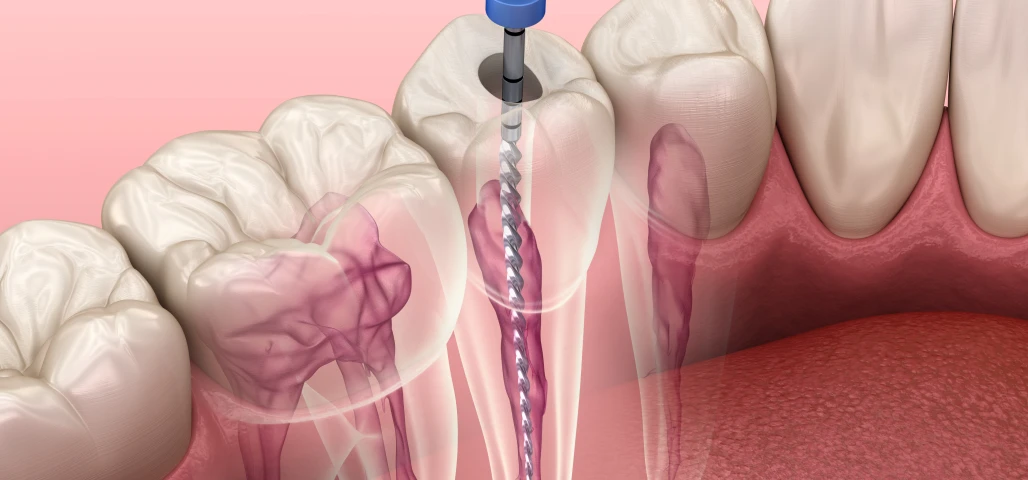

L’endodontie est la spécialité dentaire qui concerne le traitement de la pulpe dentaire, c’est-à-dire la partie interne de la dent où se trouvent les nerfs et les vaisseaux sanguins. Lorsqu’une carie profonde, un traumatisme ou une infection atteint cette zone, un traitement endodontique devient nécessaire pour préserver la dent et éviter son extraction.